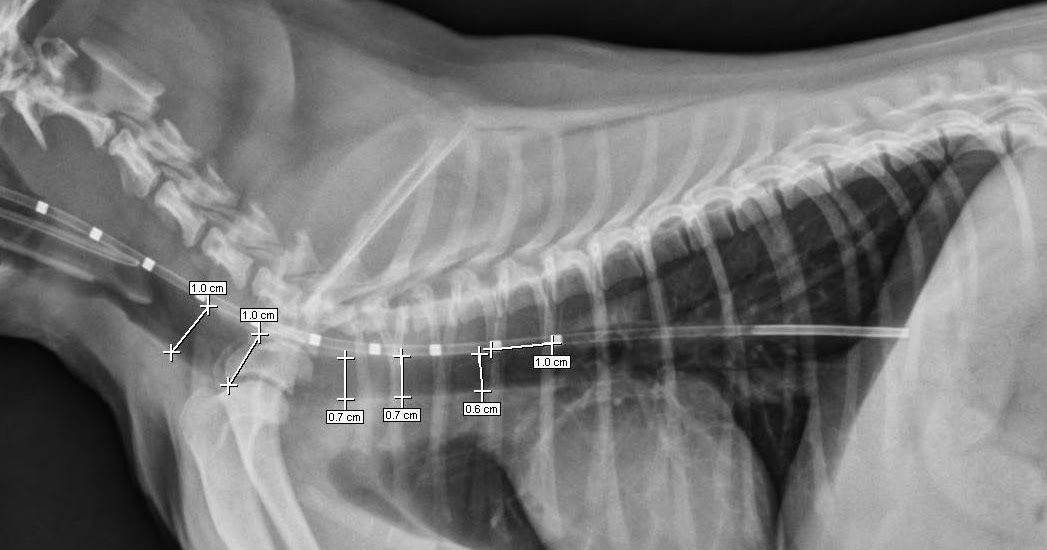

Pretreatment tracheal collapse in another patient Download Tracheal Collapse Anesthesia Tracheobronchomalacia (tbm) and excessive dynamic airway collapse (edac) are airway abnormalities that share a common feature of expiratory. Collapse of the upper airway is common during anaesthesia, and airway maintenance is a fundamental anaesthetic skill. Historically, airway collapse has been attributed to tracheomalacia (tm),. Patients are selected to undergo a trial. The indication for corrective treatment is severe central airway. Tracheal Collapse Anesthesia.